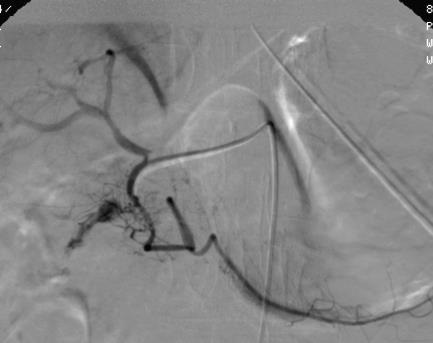

在下消化道出血栓塞中 “栓塞足够" 意味着边缘动脉发出的直动脉栓塞。

选择不足导致栓塞不足,栓塞不足时导致再出血的发生;栓塞足够往往导致器官出血,操作者需要谨慎的平衡两者。在消化道出血方面,“栓塞足亦(selective enough)” 意味着栓塞终末支的直动脉,甚至直动脉长支或短支的其中一支,最多不能连续超过三支;而上消化道出血对选择性要求相对差,栓塞足够意味着两头堵。 Ongoing bleeding / rebleeding